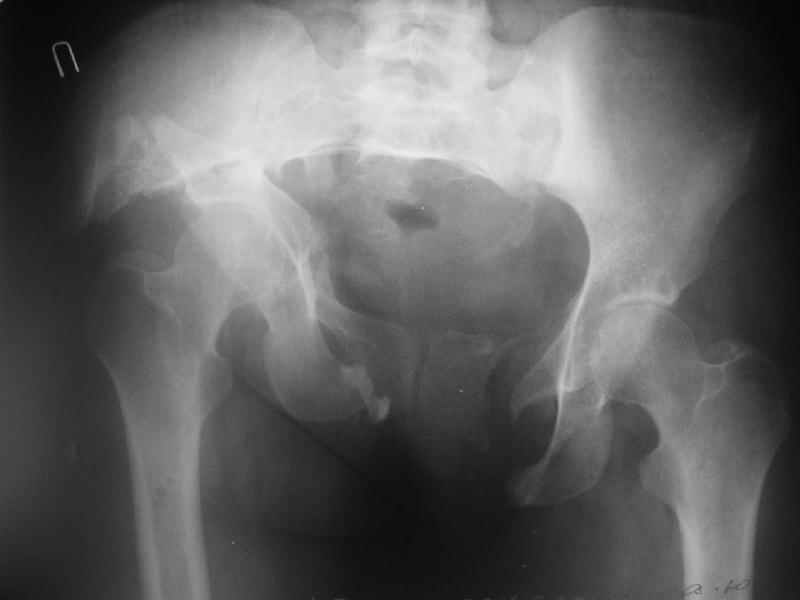

По просьбам коллег отправляем снимки таза: прямая, inlet, outlet, 2 дополнительные компьютерные томограммы.

Госпитализирована больная 27 лет. Травма 1.5 года назад, сбита авто. При поступлении в местной больнице наложен фиксационный аппарат-«передняя рама». Через месяц аппарат снят из-за нагноения, разрешена ходьба с костылями. В послеоперационном периоде отмечалось нагноение забрюшинной гематомы. При обрашении к нам 3 мес назад в области промежности имелся свищ, по месту жительства выполнено иссечение свища, был гнойный затек на бедре, откуда получено до литра гноя, больная ходила с костылями.Свищ зажил 1,5 мес назад При поступлении сейчас укорочение до 5 см, ходит без дополнительной опоры, имеется выраженная хромота.Какой, по вашему, может быть оптимальная тактика оперативного лечения? Ограничиться низведением вертлужной впадины (каким доступом?), выполнить полную реконструкцию передних и задних отделов, одномоментно или поэтапно? Заранее благодарен.

In other hand, I would like to see the primary X rays, because with 3D-CT alone I cannot classify that fracture into Letournel's classification. Maybe it is a posterior hemitransverse with anterior column fracture.

Дополнительно сообщаю, что больную беспокоят боли в области левого крестцово-подвздошного сочленения, в области правого болей нет. Кроме того, беспокоит укорочение конечности (ходит с компенсацией) без дополнительной опоры (в помещении), нарушение осанки (сколиоз, избыточный поясничный лордоз), боли в пояснице, невозможность стоять более 20-30 минут, спать без резинового круга под крестцом и подушкой под коленями, неудобство при сидении. Majeed 41 балл.